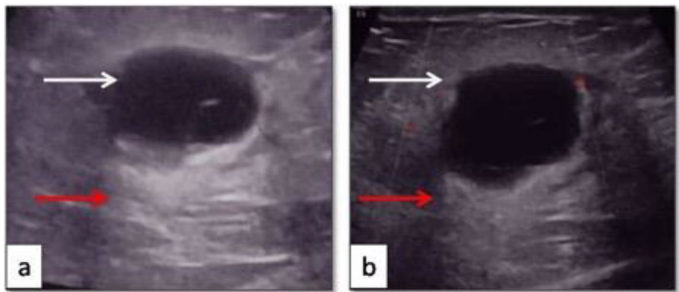

乳腺肿块常引发对恶性肿瘤的担忧,但某些罕见炎症性疾病可能表现出相似临床特征。嗜酸性乳腺炎作为良性炎症性疾病,在文献中仅少数病例记载,多与哮喘、Churg-Strauss综合征或高嗜酸细胞综合征相关,且通常伴有外周血嗜酸细胞增高。当患者同时出现周期性瘙痒性皮肤病变时,诊断更为复杂。本文报道的病例挑战了这一传统认知:患者乳腺肿块影像学呈现恶性特征(BIRADS 4级),但外周嗜酸细胞计数(AEC)仅72/μL,血清IgE水平正常(21 IU/ml),揭示了嗜酸性乳腺炎诊断的新维度。

患者以无痛性右乳肿块就诊,既往两年春季反复发作瘙痒性红斑丘疹/水疱,皮质激素治疗有效。影像学提示恶性可能,但病理活检揭示本质为良性炎症。